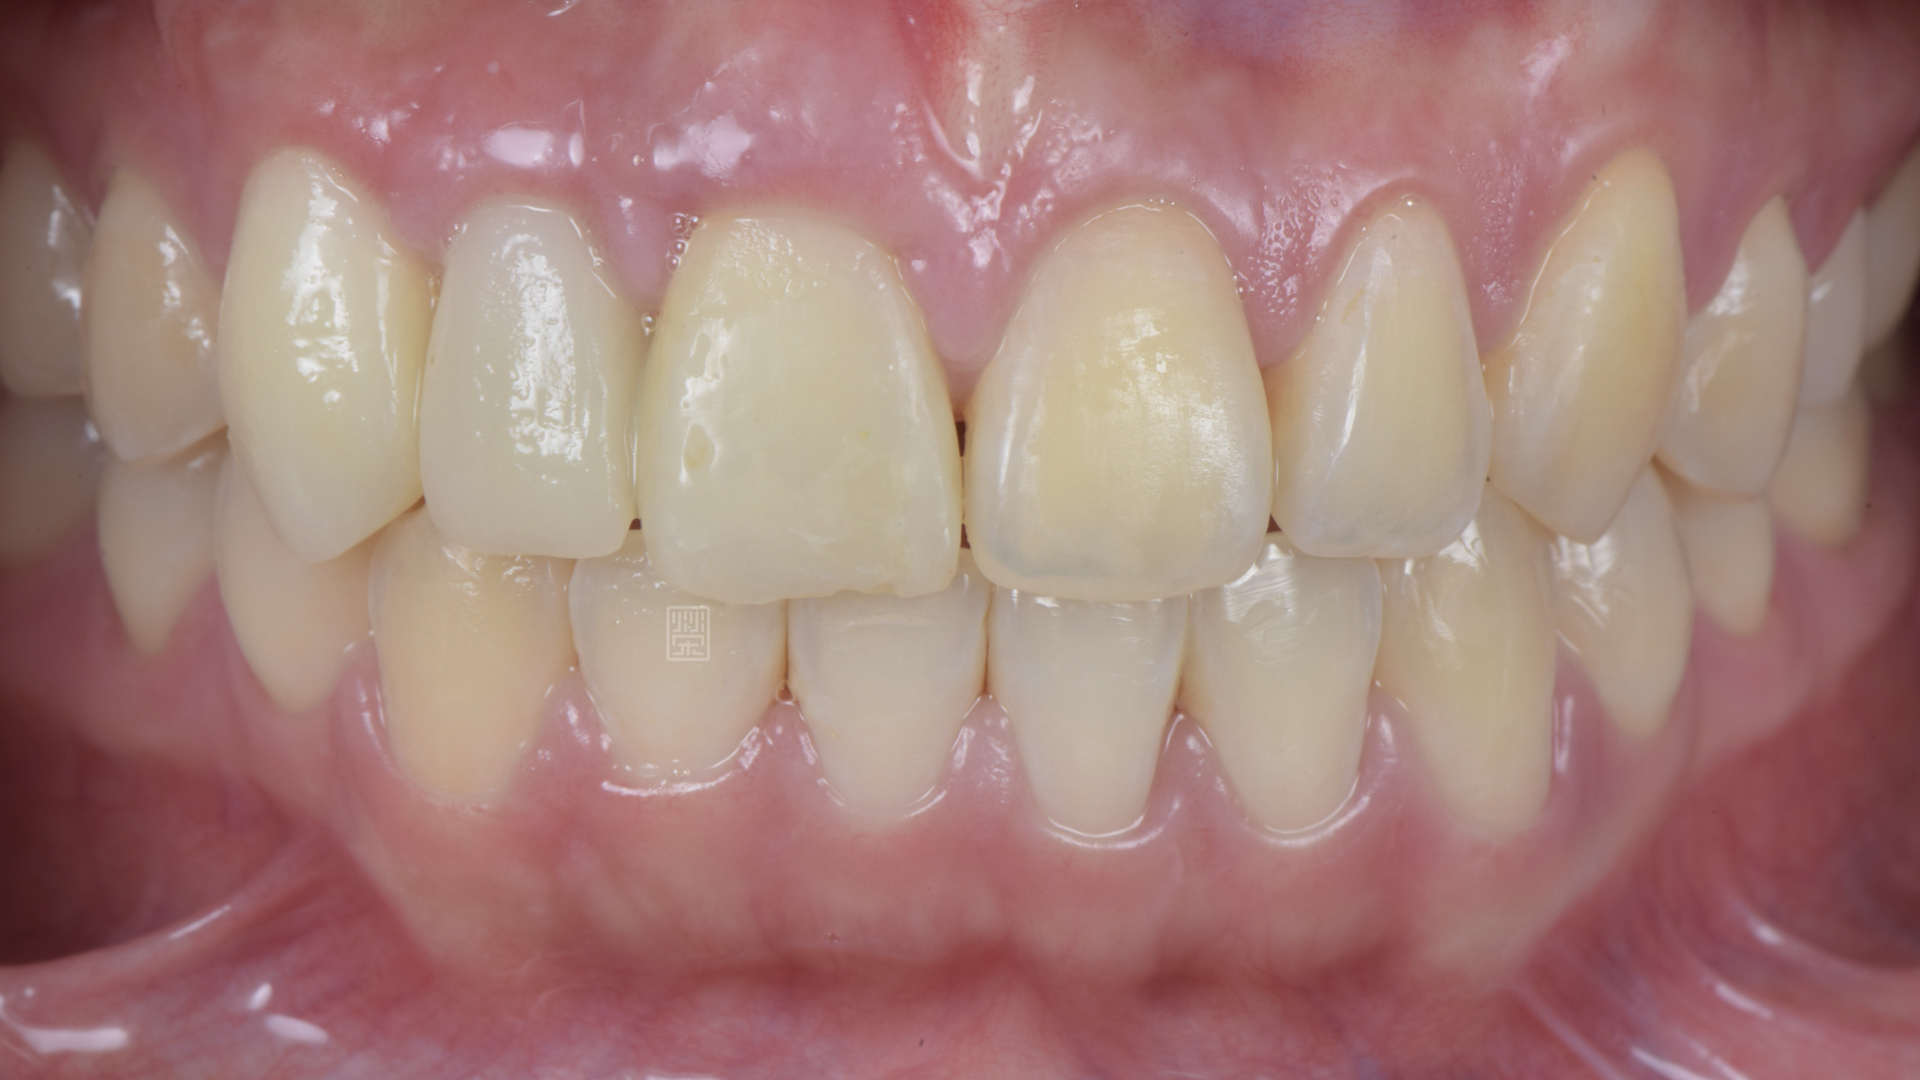

全瓷冠、植牙全瓷冠完成